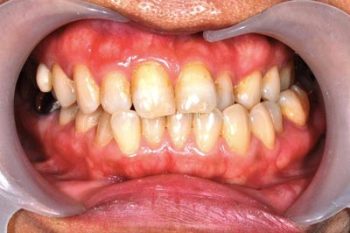

治療前

治療後